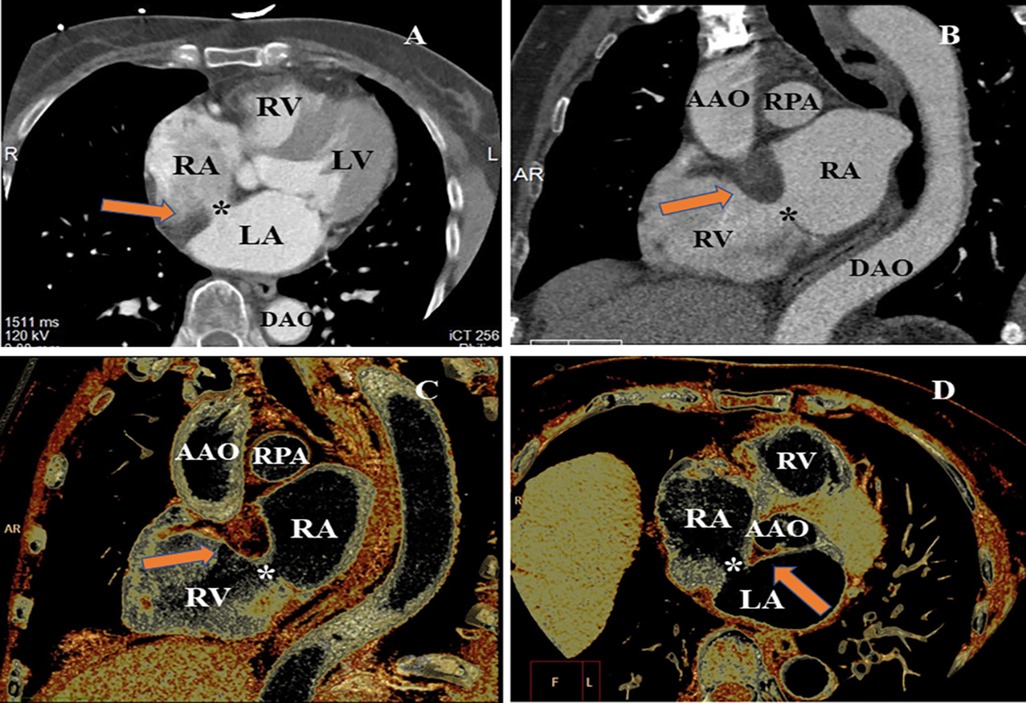

A cardiac computer tomography angiography (CCTA) scan was performed to further characterize the atrial septum and evaluate the status of the coronary artery. The CCTA images demonstrated a 9 mm × 13 mm defect on the atrial septum (Figures 2A,B). The volume rendering image of the CCTA scan showed a non-enhancing, smooth, well-marginated mass with an appearance similar to subcutaneous fat (Figures 2C,D). In addition, the CCTA scan revealed a myocardial bridge in the middle of the left anterior descending artery.

Figure 2. CCTA evaluating the LASH with ASD from different perspectives. (A) MPR image of CCTA found the loss of echogenicity between the left atrium and the right atrium (*). (B) MPR showed significant hypertrophy of the atrial septum (arrow), producing a dumbbell shape. (C) VR image indicated the thickened interatrial septum (arrow). (D) VR image of CCTA demonstrating the ASD and significant hypertrophy of atrial septum (arrow and *). MPR, multiplanar reconstruction; VR, volume rendering; LV, left ventricle; RV, right ventricle; RPA, right pulmonary artery; AAO, ascending aorta; DAO, descending aorta.